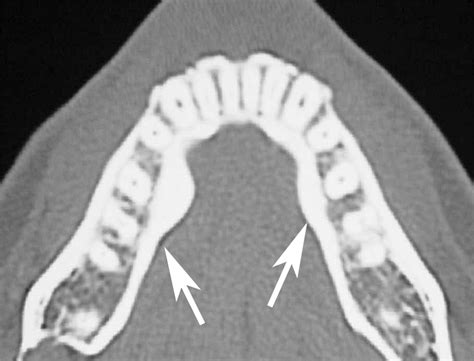

• Torus Palatinus: These occur on the hard palate, which is the roof of the mouth. They often appear as a singular or lobulated bony mass located in the center of the palate.

• Torus Mandibularis: These appear on the lingual aspect of the mandible, which is the inner side of your lower jaw, usually located near the premolar teeth. They are often bilateral, meaning they appear on both the left and right sides of the jaw.